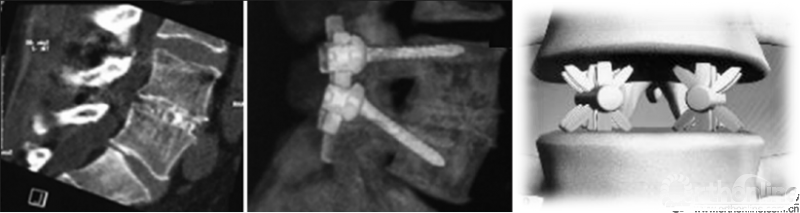

PE-TLIF为经椎间孔入路,使用上关节突导向切除装置定向磨除上关节突,扩大椎间孔区域,在10mm脊柱内窥镜辅助下进行腰椎的减压、椎间植骨及融合器植入,最后辅以经皮置入椎弓根螺钉。

该技术集内镜技术、通道技术、经皮置钉技术、高度可调新型融合器于一体,拥有自主研发的融合器和自行探索的手术方案,是一款完全国产的新技术,并已获得自主知识产权。该技术已达到精准诊断、精准医疗的国际脊柱微创水平。

针对以上问题,海涌教授和杨晋才教授团队自主创新设计了经皮内镜辅助下经椎间孔腰椎减压融合术(Percutaneous Endoscopic Transforaminal Lumbar Interbody Fusion, PE-TLIF)以及配套的手术相关器械,初步临床结果令人满意,无神经损伤和融合器移位等并发症发生。